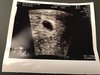

Dziewczyny, bardzo Was przepraszam ale malo sie udzielam bo po pierwsze z braku czasu, chodze spac codziennie o 21 najpozniej. Po drugie troche tez chyba ze stresu, czasami na fejsie sie udzielam ale to tez sporadycznie. A wiec beta z wczoraj 4200 (17dpt) a dzis na usg jest pecherzyk ciazowy. Poki co podchodze spokojnie ale doktor mowi ze wszystko wyglada ok, progesteron znow nisko sie pokazal ale czekam na kontakt z kliniki i zobaczymy, moze zastrzyk dolozymy.